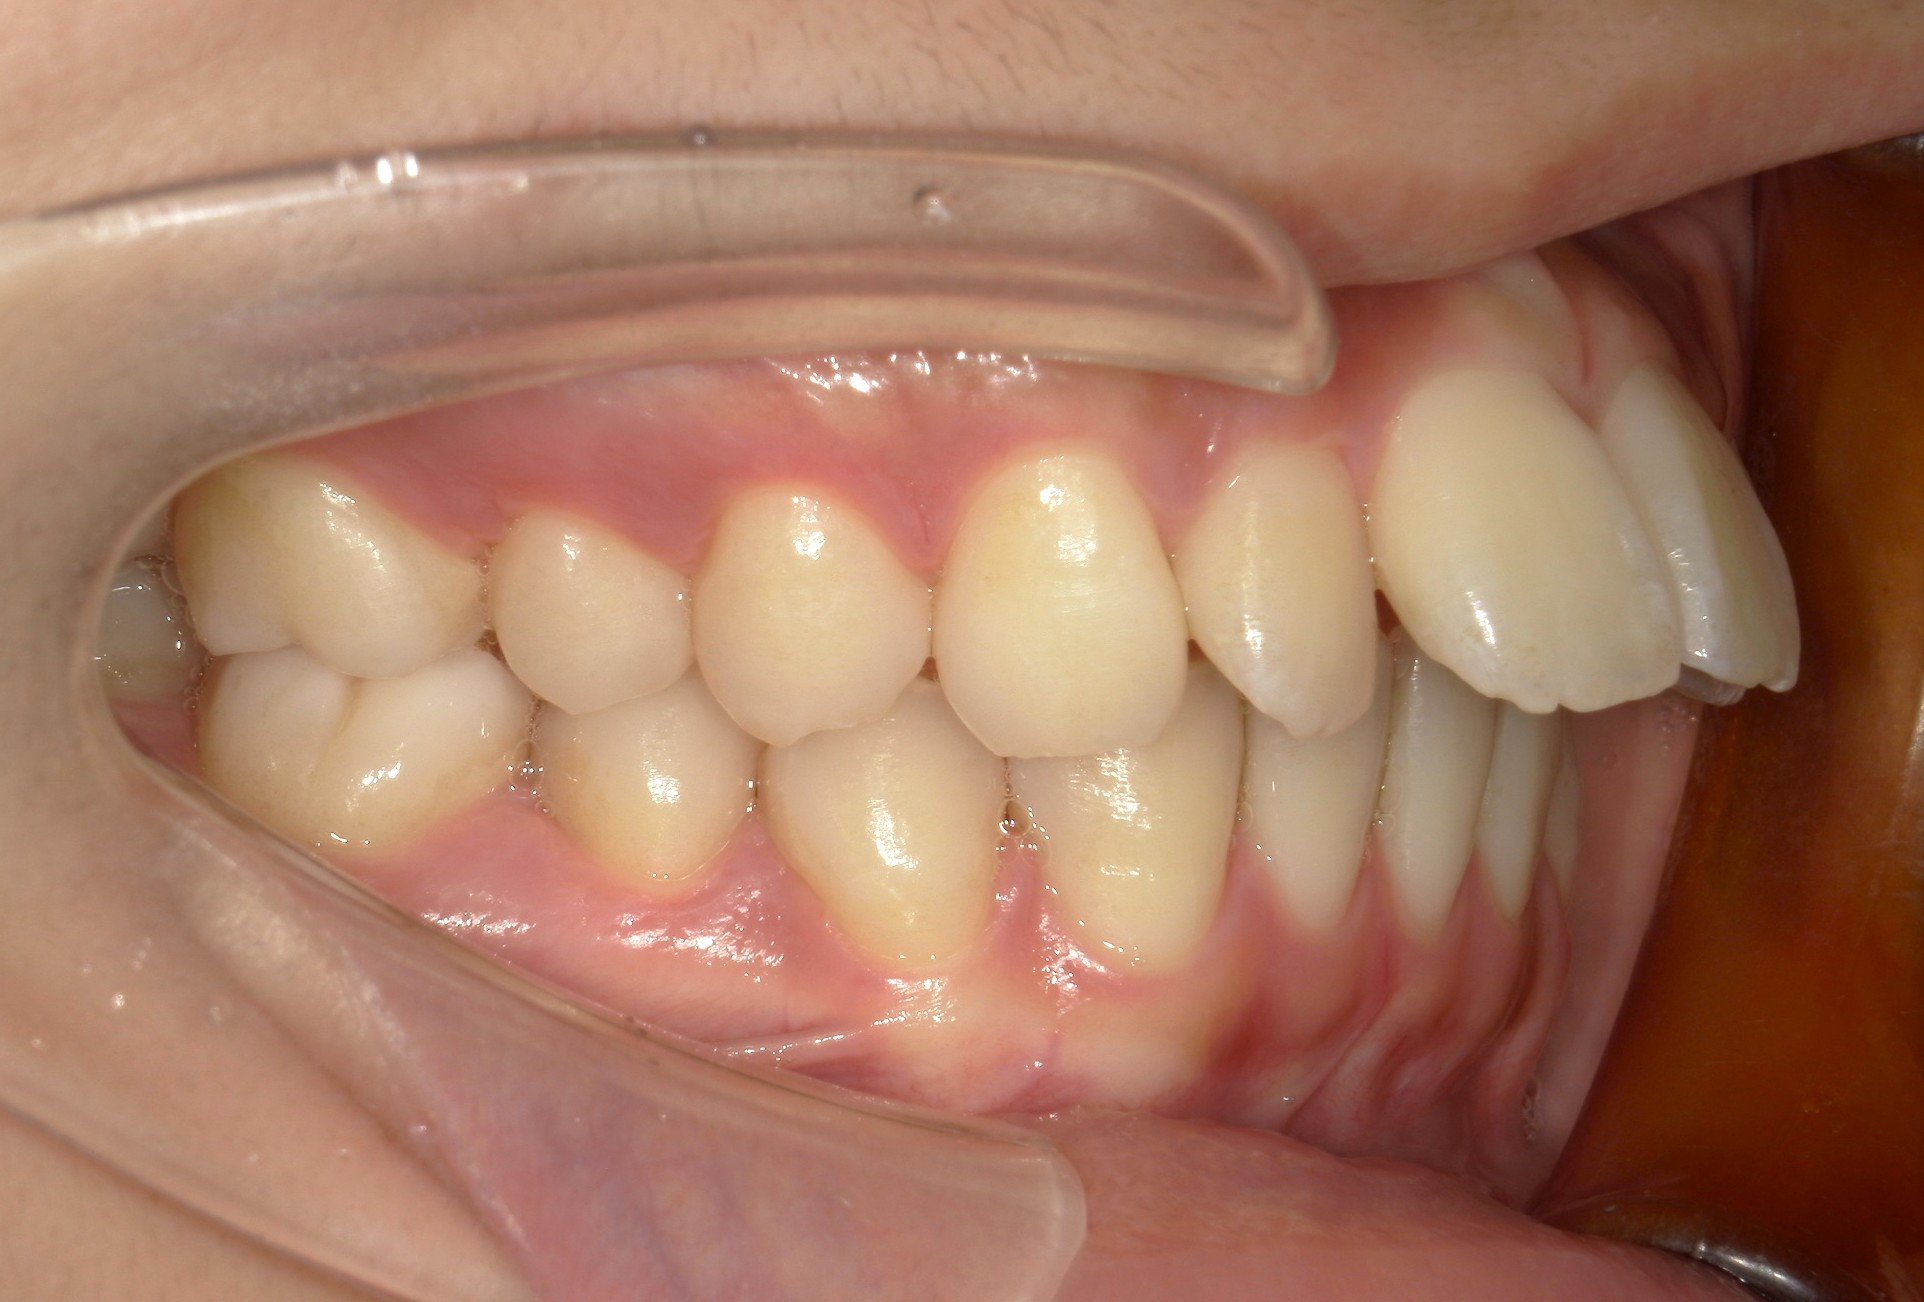

横から見た口腔内写真でよくわかるように、前歯が出っ歯になっており、全く咬んでいない状態でした。また下の前歯が本来4本あるところが、先天的に一本少なく3本しかない(Three incisors)であったため下顎のアーチが小さいというお口の状態でした。前歯を正しい傾きに治し、咬合させるため、上の歯のみ2本の抜歯を行うこととしました。下の前歯が3本のため、その正中に注意しながら前歯の傾きを修正し、奥歯のポジションを整えて仕上げました。口元の突出感は大きく改善し、咬合も良好な状態で完了することができました。

口内右

治療前

治療後